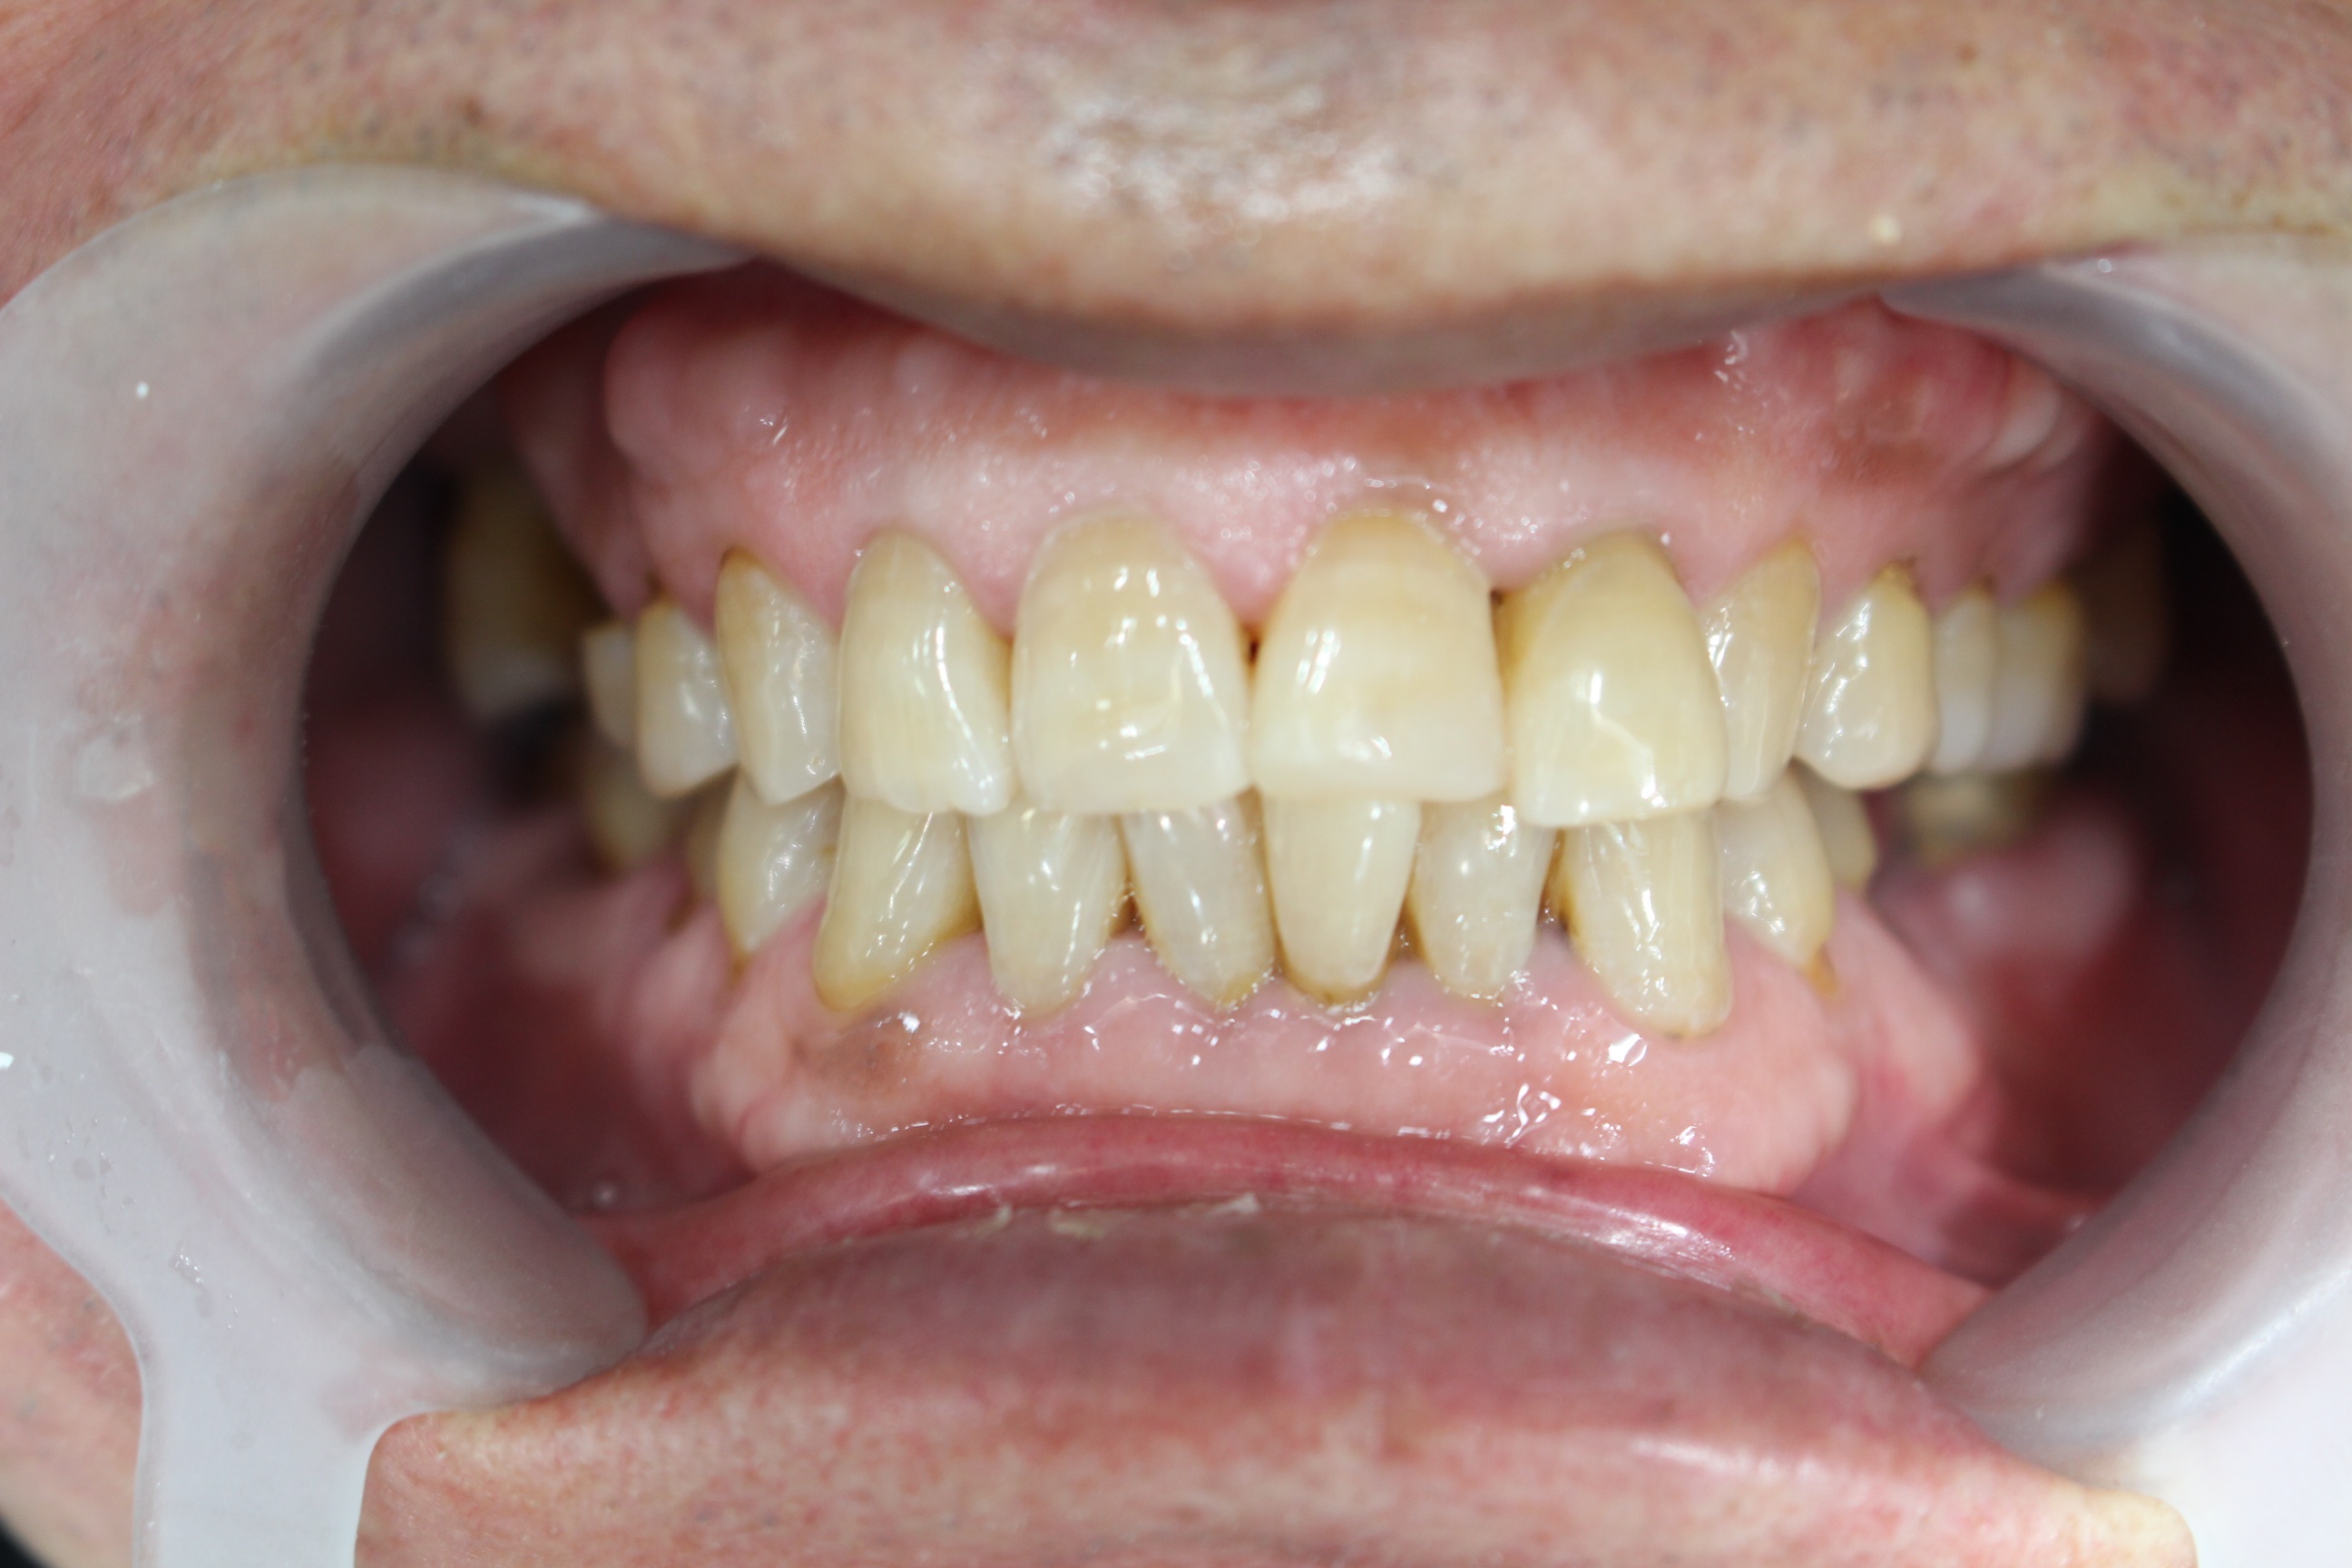

수술 전

수술 후

구치부 임플란트 식립사례

전후사진